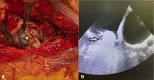

Caval isolation with balloon catheters within venous cannulas in cardiac surgery